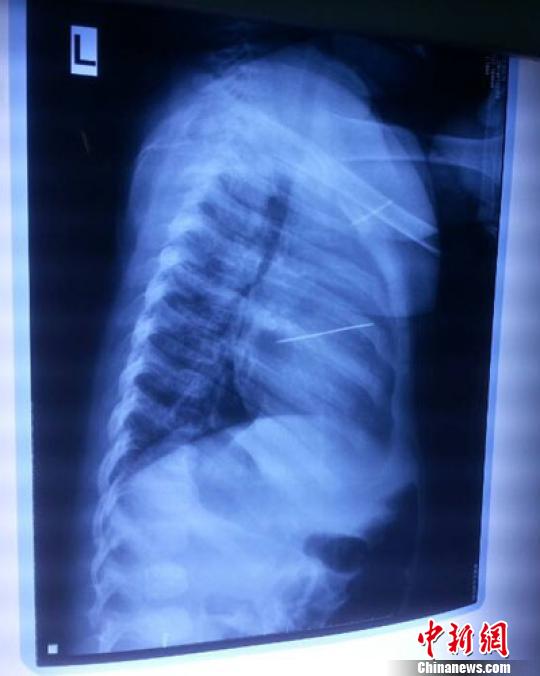

女嬰胸片提示心臟里面扎了一個(gè)縫衣針 蔡迅翔 攝

醫(yī)院胸心外科主任翟波介紹說(shuō),1月22日,小患者彤彤因?yàn)榘l(fā)燒抽搐來(lái)醫(yī)院就診,常規(guī)檢查時(shí)發(fā)現(xiàn)孩子心臟里面扎了一個(gè)縫衣針。

“第二天上午,我們做了個(gè)緊急彩超檢查,發(fā)現(xiàn)針是從患者右心室表面刺入,穿破室間隔,到達(dá)左心房,中間還有一部分損害到二尖瓣。于23號(hào)下午,我們就做了一個(gè)緊急手術(shù),手術(shù)中發(fā)現(xiàn),這枚針已經(jīng)刺入心臟,沒入了右心室的下面,表面已經(jīng)看不到針了,僅能看到一個(gè)小針眼,還在往外滲血,一點(diǎn)一點(diǎn)的滲,心包腔里面大概有100多毫升的出血,心包上一個(gè)洞,針在右心室表面刺入以后,穿過(guò)室間隔,在二尖瓣的上方,進(jìn)入了左心房,在針的四周,有很多纖維沉積物,包繞著這枚針。”翟波說(shuō),他們把針取出來(lái)以后,測(cè)量了一下,長(zhǎng)度大概是五厘米,同時(shí)發(fā)現(xiàn)這個(gè)針給患者左心房的后壁造成了一定的損傷,左心房的后壁已經(jīng)損傷了三分之二,還剩下有左心房的外膜,很薄的一層,如果這一層再破的話,這個(gè)孩子將會(huì)引起大出血,很快就會(huì)死亡。